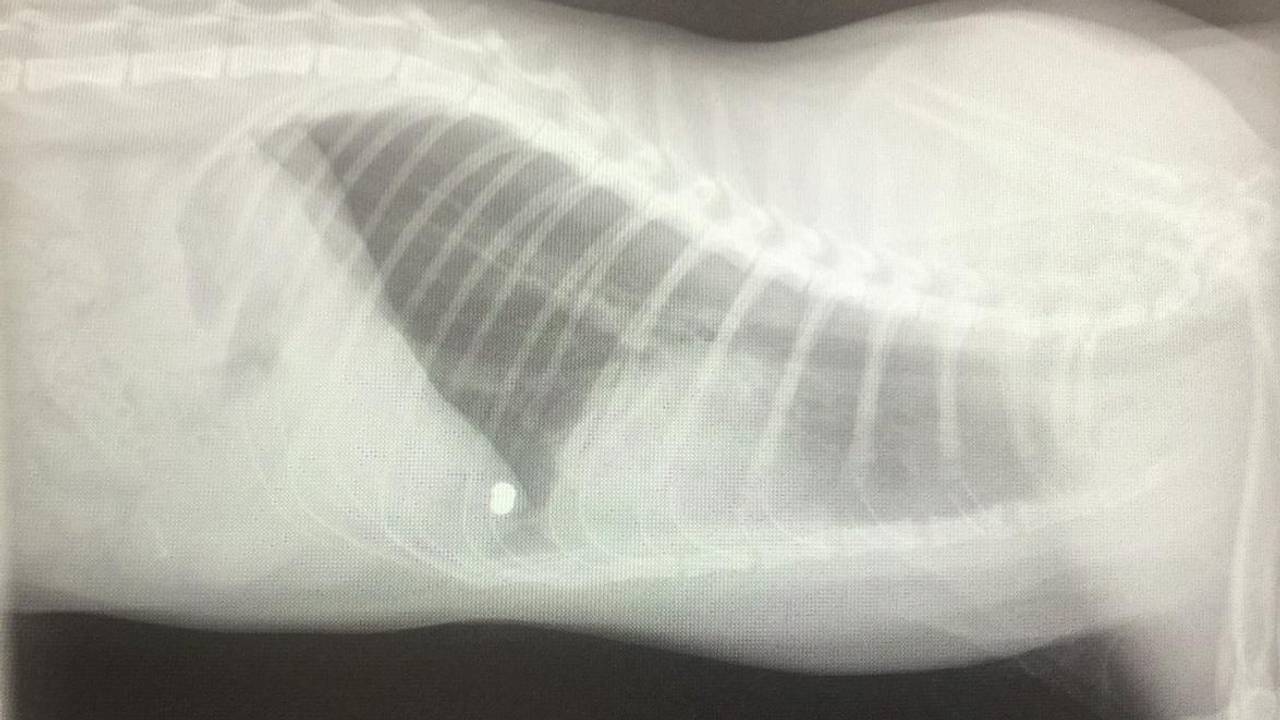

Eenmaal daar bleek dat Tijger een kogel in zijn lichaam had zitten. "Die heeft op twee millimeter na zijn hart gemist. Hij zit tegen zijn long aan. Alle borstspieren zijn gescheurd, zijn borstbeen is gebroken en hij ademt heel moeilijk. Hij eet ook niet vanwege de pijn, Tijger krijgt sindsdien sondevoeding."

Hij werd direct geopereerd, maar de kogel is niet uit het lichaam van Tijger te krijgen. "De kogel zit te dicht tegen zijn long aan. De dierenarts zag dat het een hagelpatroon is, dus we weten zeker dat er met een luchtbuks is geschoten."

De kogel blijft dus in het lichaam van Tijger zitten. "We moeten wachten tot de kogel vanzelf gaat zwerven door zijn lichaam. Het is maar hopen dat die geen organen beschadigt of terechtkomt op een plek waar ze hem wel kunnen verwijderen." Het is nog maar de vraag of Tijger het overleeft. "Het kan best dat hij dan na een paar maanden weer ziek wordt omdat er iets gebeurt met die kogel. En hij zal de rest van zijn leven medicatie nodig hebben."